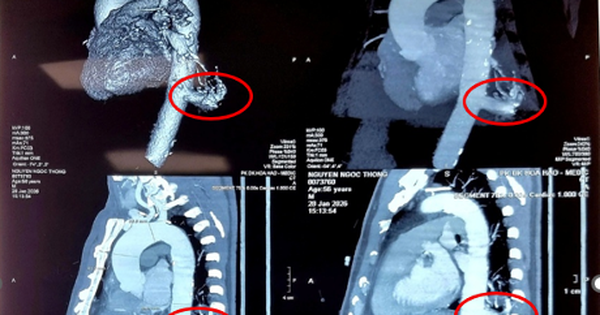

Việt Nam lần đầu dùng robot mổ điều trị phổi biệt lập thành công

Lần đầu Bệnh viện Bình Dân mổ robot điều trị phổi biệt lập, loại bỏ khối nguy cơ vỡ mạch chủ, bệnh nhân xuất viện sau 4 ngày, hồi phục nhanh.